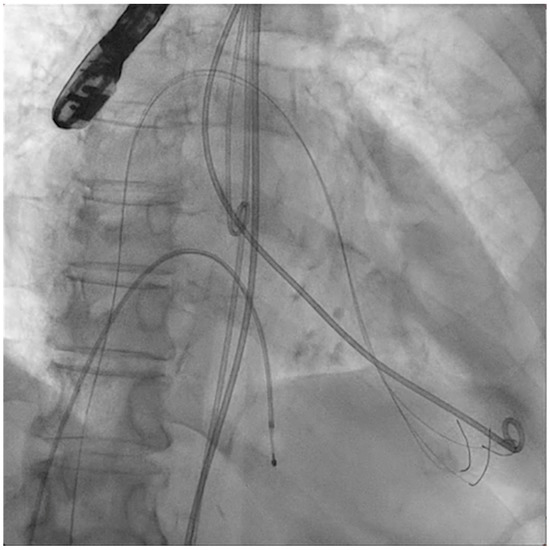

The next steps consist of crossing the mitral valve with three long high-support 0.014´´ wires downstream into the left ventricle (LV) (Figure 2) and then advancing three lithotripsy balloons (Shockwave Medical) across the mitral valve; with rapid pacing (120 beats/min), simultaneous inflations of all balloons will deliver a total of 90 pulses from each balloon (Figure 3). Finally, access to the LV has to be attained again with the Safari wire to complete PMC with large balloons appropriately sized to the mitral valve area and diameters (Figure 4). Embolic protection devices are encouraged to avoid neurological or systemic ischemic events due to calcific debris.

Figure 3.

Simultaneous inflation of three 7 × 60 mm shockwave balloons on the mitral valve for lithotripsy applications.

Figure 4.

Percutaneous mitral commissurotomy (non-compliant 26 mm balloon).